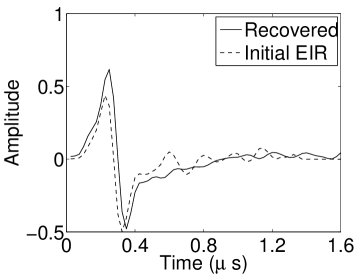

The reconstruction region ( mm2) was represented by pixels with pixel size mm in each dimension. The initial guess of the EIR employed in the VP algorithm was different than the EIR that was assumed when generating the simulated data. This served to simulate a situation in which an experimentally measured EIR contained errors.

Each element in a real-world transducer array possesses its own EIR. In practice, the differences between the EIRs are sometimes neglected and an EIR corresponding to a single element may be used to represent all elements in the array. In some of the studies below, the EIR employed to initialize the VP algorithm (EIR-2 in Figure 1(b)) and the EIR employed to produce the simulated measurements (EIR-1 in Figure 1(b)) were experimentally measured from two different transducer elements in a circular transducer array (see Sec. VI-B). EIR-1 was measured by temporally integrating the PA signal produced by a point source positioned at the focus of the transducer. EIR-2 was measured by use of the method reported in [RNR2011]. In order to investigate the sensitivity of the VP algorithm to the initialization of the EIR, we employed different EIRs obtained by degrading EIR-1 as described later. When solving the sub-problem in Line-2 of Algorithm 1, was initialized as the zero vector. Algorithm 1 was terminated after 500 iterations, since it was observed that the changes in the reconstructed images with more iterations were negligible. When implemented by use of a single core of an Intel Xeon E5-2640 CPU, each iteration required approximately 7s to complete.

As shown in Figure 6, when the error in the EIR was small (e.g., as with the EIR in Figure 6(a)), images were reconstructed with high accuracy using the VP algorithm. When the perturbations in the EIR were stronger (e.g, as in Figure 6(c)), artifacts and distortions in the reconstructed images were still significantly reduced by use of the VP algorithm; however, larger values of the regularization parameters had to be applied. When as in the initial EIR in Figure 6(e), no improvement was observed in the image reconstructed by use of the VP algorithm.

Figure 7(a) reveals that use of the inaccurate EIR in the conventional iterative method created strong artifacts and distortions. Figures 7(b) confirms that the artifacts and distortions were significantly mitigated when the VP method was employed. Image profiles for both cases are shown in Figures 7(c). The overall accuracy of the recovered EIR, shown in Figure 7(d) and 7(e), was improved, but it contained spurious oscillations.